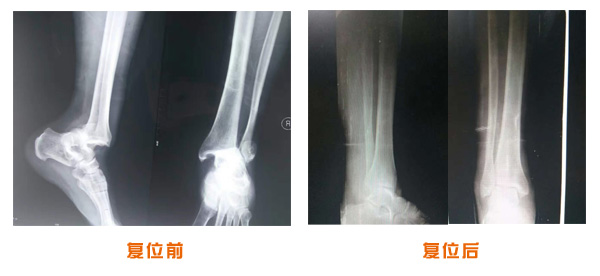

肥城市安駕莊梁氏骨科醫(yī)院是一所以梁氏手法正骨配合膏藥為特色的現(xiàn)代化??漆t(yī)院。

梁氏骨科術(shù)始創(chuàng)于清雍正年間,歷經(jīng)八代,至今已有三百年歷史。據(jù)1929年泰安縣志載“梁瑞圖先生,字增生,號蓮峰,安駕莊人,精岐黃并發(fā)明接骨,凡跌打車凡跌打車軋皮不破而碎骨者......【詳細(xì)】 |